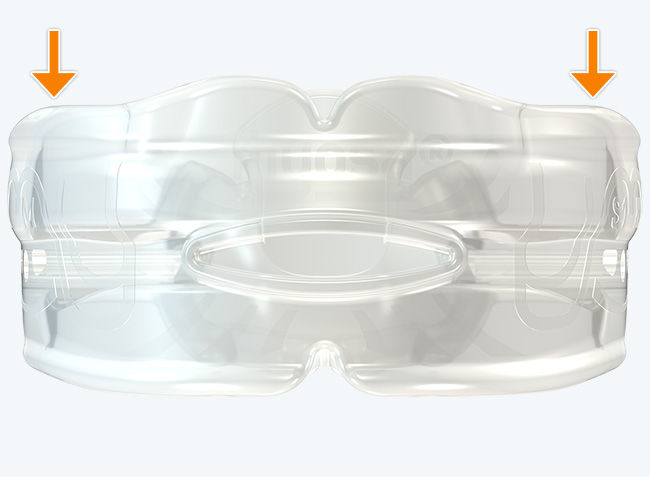

The Myosa® for TMJBDS® S1H is specifically designed for patients who are breathing and disordered sleep (BDS) primary with moderate to severe BDS as indicated by a Breath Hold Time (BHT) of 20 or less. These patients may or may not have TMJ disorders, but due to the severity of their BDS, they require immediate improvement of their airway. The features of the appliance not only work to open the airway, but also allow patients to undertake initial exercising of the lip, tongue and airway muscles. Progress to the S1 when the patient’s BHT reaches 20 seconds or more.